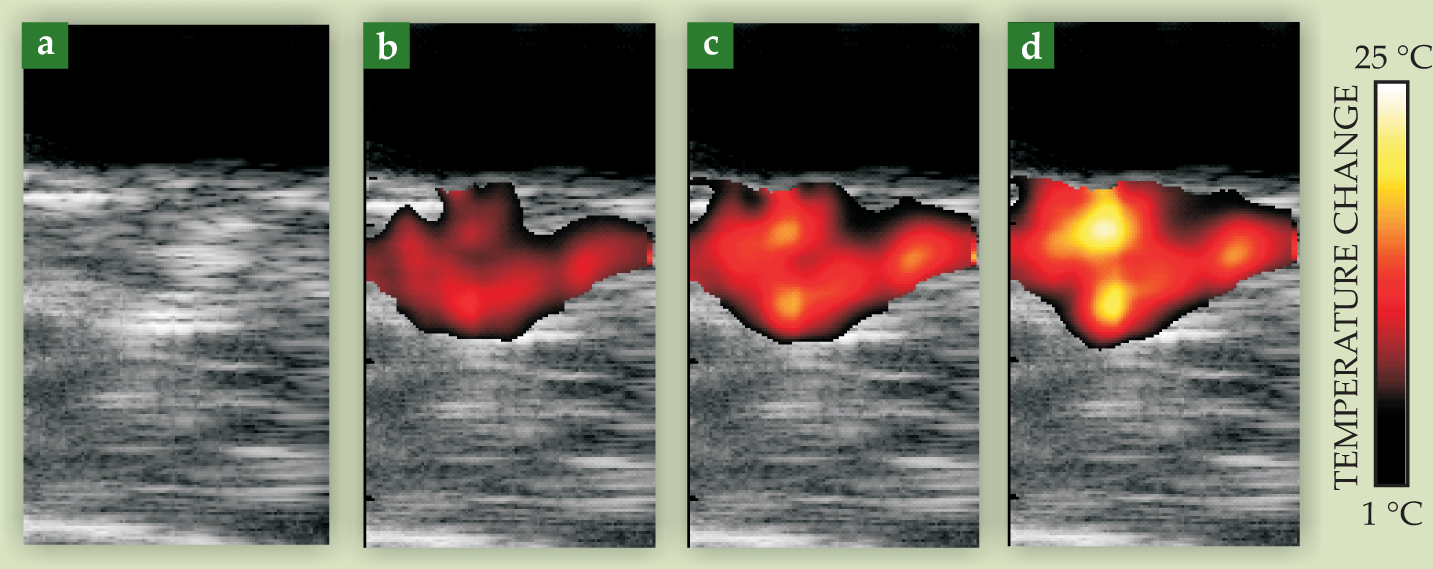

The dimensionless Grüneisen parameter, one factor in the expression for the photoacoustic pressure amplitude, is temperature dependent. 17 Photoacoustic images can therefore be used to monitor changes in tissue temperature during photothermal therapy, as shown in figure 6. A tumor-bearing mouse was injected with gold nanorods targeted to the tumor. A continuous-wave laser tuned to the nanorods’ maximum absorption wavelength provided the therapeutic source, and photoacoustic imaging was performed with a pulsed laser operating at the same wavelength. One hour after nanorods were injected, photothermal therapy was applied for three minutes. Ultrasonic and photoacoustics-based thermal images acquired after 60, 120, and 180 seconds of laser irradiation show a gradual increase in temperature as therapy progresses—at the end of the three minutes, the tumor temperature was elevated by more than 20 °C. Histological evaluation after the procedure confirmed that the tumor had indeed been thermally damaged—evidence of the significant role that photoacoustics can play in optimally delivering molecular therapy.

Figure 6. Photoacoustic imaging of temperature during photothermal cancer therapy of a tumor-bearing mouse. The mouse was injected with optically absorbing gold nanorods targeted to a protein in the cancer cells. The tumor region was then irradiated with continuous-wave laser light at the nanorods’ peak absorption wavelength. Images taken after (a) 0, (b) 60, (c) 120, and (d) 180 seconds of treatment show the temperature rise in the tumor. Each image represents a 10.5-mm by 20-mm field of view.